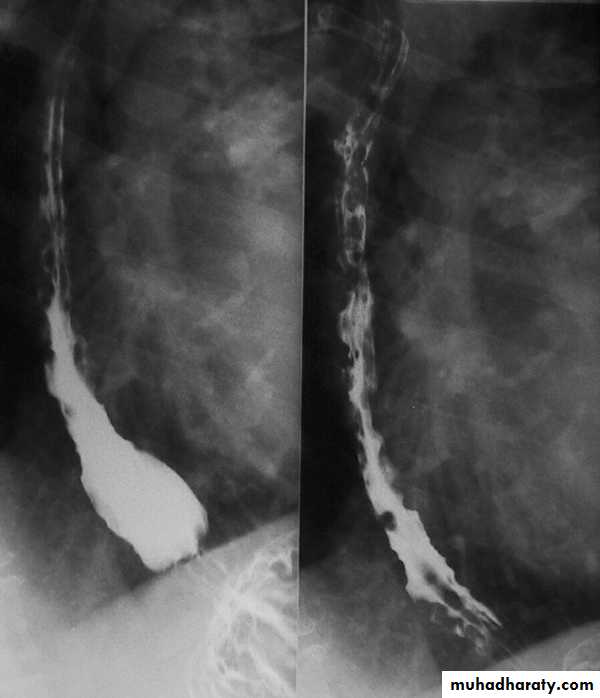

A chalasia Cardia

A : AbsenceChalasia : Relaxation

Narrowing :

1-the narrowing is Constant Short length (confined to cardia).

2-Regular and smooth.

3- No shouldering sign.

4-Tapering (Tip of pencil , cigar shape) Under left dome of diaphragm.

Achalasia continue

5. DILATATION (Sac like in proximal part )6-Undulating or spiky out line due to sluggish peristalsis.

7 Non- homogeneity of Barium due to food particles.

8-Air Barium level.

9- CXR shows widening of mediastinum.

10-Absence of fundal gas shadow.

7-Basal fibrosis in lungs due to repeated aspiration pneumonia .